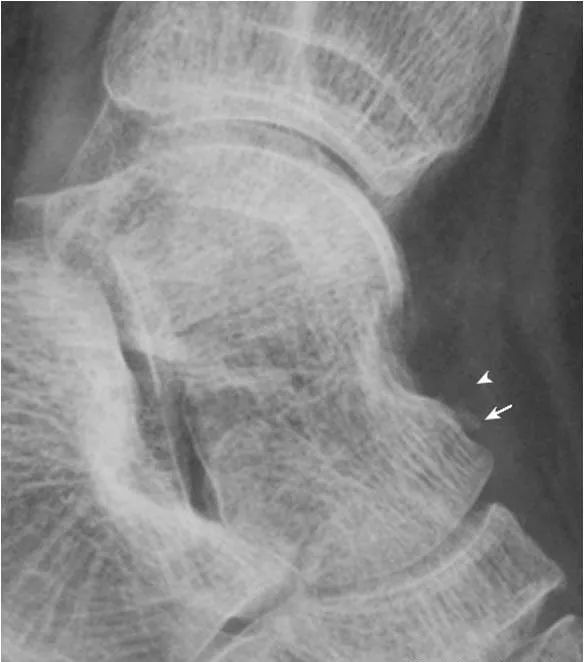

3.跟骨生理透亮区:

正常人跟骨可见三角形的局限性透亮区,为生理性骨小梁稀疏区(箭头),透亮区内骨小梁仍清晰可见。与骨囊肿和脂肪瘤不同,两者因存在骨质破坏,骨小梁显示中断。

4.跟骨上副骨:

呈跟骨上方、三角骨(白箭头)后方骨性结节(箭),为正常变异。腓骨副骨(黑箭头)与距骨重叠。